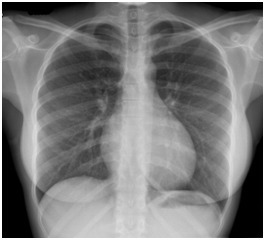

Bilan de base devant une neutropénie fébrile sans porte d’entrée infectieuse clinique : – radiographie thoracique ; – ECBU ; – hémocultures sur PAC+ ; – dans le Pilly : coproculture + prélèvement de gorge. Non réalisés en pratique.

Vous avez donc instauré une antibiothérapie probabiliste large spectre par pipéracilline-tazobactam et réalisé un bilan microbiologique avec des hémocultures sur chambre implantable et en périphérique, un ECBU. La radiographie thoracique est la suivante (figure 4) : Fig. 4 (source : M. Roulleaux Dugage) L’ECBU est stérile. La situation clinique se dégrade avec l’apparition de signes d’hypoperfusion périphérique, révélant un choc septique. La patiente est transférée en réanimation, où est instauré un support vasopresseur par noradrénaline, permettant de la stabiliser. Vous recevez dans le même temps un appel du bactériologue : les hémocultures vous reviennent positives à Staphylococcus aureus en 8 heures sur la chambre implantable et en 11 heures sur la veine périphérique.

La radiographie thoracique est normale. Devant le différentiel de pousse > 2 heures en faveur du PAC, on retient le diagnostic d’infection de PAC. Il existe une indication formelle à retirer le PAC en cas d’infection de PAC si : – signes d’inflammation locale (pus, érythème…) ; – germes : Staphylococcus aureus, Candida albicans ; – mauvaise tolérance hémodynamique.